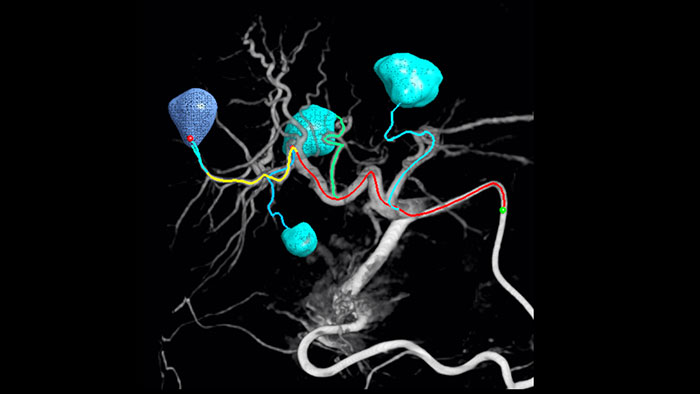

Détection automatique des vaisseaux nourriciers avec EmboGuide.

Détection automatique des vaisseaux nourriciers avec EmboGuide

Notre solution de détection automatique des vaisseaux nourriciers améliore de manière significative la détection des artères nourricières par rapport à l’utilisation de la tomographie à faisceau conique seule. EmboGuide vous aide à maximiser l’efficacité de vos procédures de chimio-embolisation transartérielle en améliorant votre sensibilité, en réduisant les faux positifs et en maximisant la concordance entre les lecteurs .1